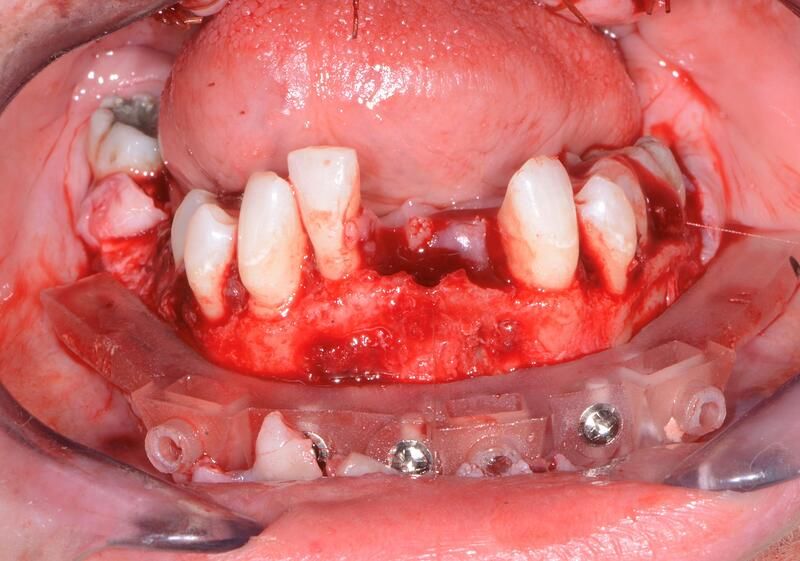

術(shù)中過(guò)程